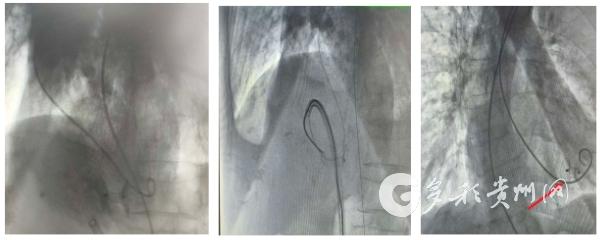

2026年2月2日,在超声科团队的密切配合下,心血管内科主任文金荣带领团队采用局部麻醉,通过股动静脉穿刺建立微创通道,借助影像学设备精准定位,顺利完成封堵器植入,手术全程历时约1.5小时。